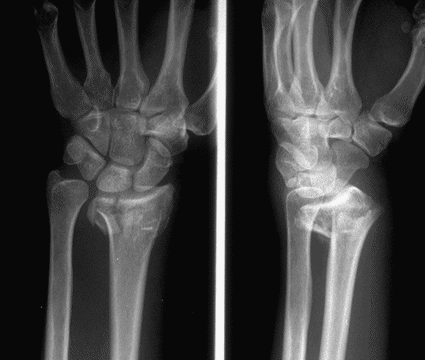

Case 1 Injury

Case 2 Preop

Case 3 Preop

Case3 Preop

Case 4 Preop

Case 5 Preop

Case 6 Preop

Case 7 Preop

Case 8 Preop